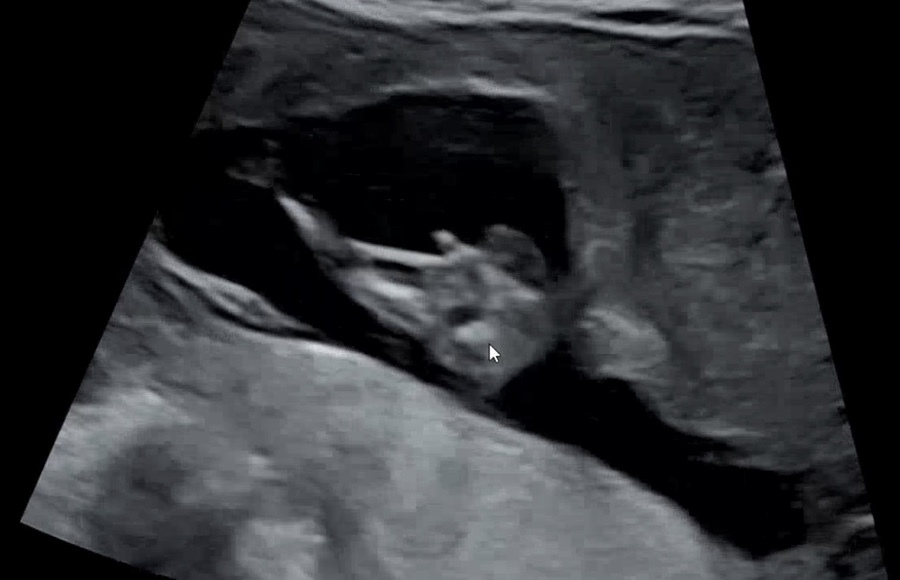

그런데 또 다른 방법도 있다.

성기 끝모양 관찰

이 방법은 성기 끝모양이 뭉툭하면 남, 열려있으면 여로 판단하는 방법이다.

이건 처음에 올린 우리 아들 사진인데, 성기 끝이 뭉툭하다. (잘 닫혀있다)

이건 둘째의 사진인데 그렇게 치면 좀 다르긴 하다.

다시 돌아가 처음의 각도법도 보자!

마지막 사진의 성기 부분!

끄트머리가 다른 게 느껴지는 느낌!